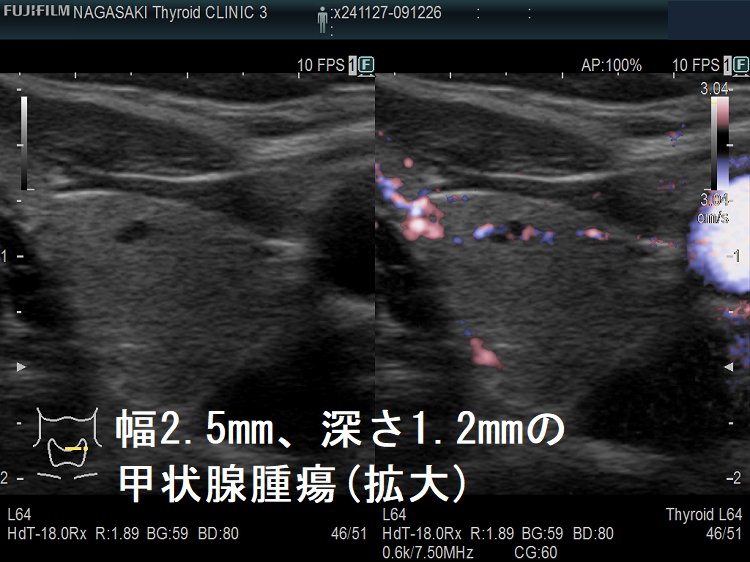

ケース③ 幅2.5mm、深さ1.2mmの甲状腺腫瘍

幅2.5mm、深さ1.2mmの甲状腺腫瘍 超音波(エコー)画像

幅2.5mm、深さ1.2mm、高さ1.6mm の甲状腺腫瘍 超音波(エコー)画像;B-モードでは甲状腺のう胞(甲状腺嚢胞)甲状腺腫瘍か判別できません。

幅2.5mm、深さ1.2mmの甲状腺腫瘍 超音波(エコー)画像 パワードプラー

幅2.5mm、深さ1.2mm、高さ1.6mm の甲状腺腫瘍 超音波(エコー)画像 パワードプラーモード; 内部微細血流を確認できるため、甲状腺腫瘍であるのが判ります。

[eFlow(イー フロー)]で内部微細血流を確認できるため、甲状腺腫瘍なのが判ります。

幅2.5mm、深さ1.2mmの甲状腺腫瘍 超音波(エコー)画像(拡大)

幅2.5mm、深さ1.2mm、高さ1.6mm の甲状腺腫瘍 超音波(エコー)画像 パワードプラーモード(拡大)

幅2.5mm、深さ1.2mmの甲状腺腫瘍 超音波(エコー)画像eFlow(拡大)

幅2.5mm、深さ1.2mm、高さ1.6mm の甲状腺腫瘍 超音波(エコー)画像 eFlow(イー フロー)モード(拡大)